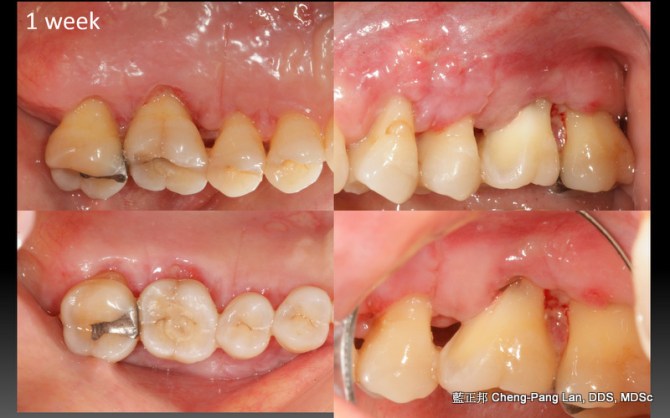

Root Amputation – Case A

This entry was posted in Treatment of Furcation-Involved Teeth and tagged Furcation, Root Amputation. Bookmark the permalink.